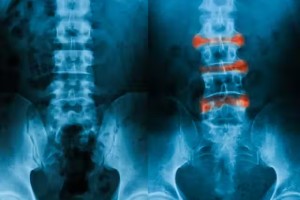

强直性脊柱炎

一种影响脊柱的炎性关节炎,导致腰部疼痛和僵硬。